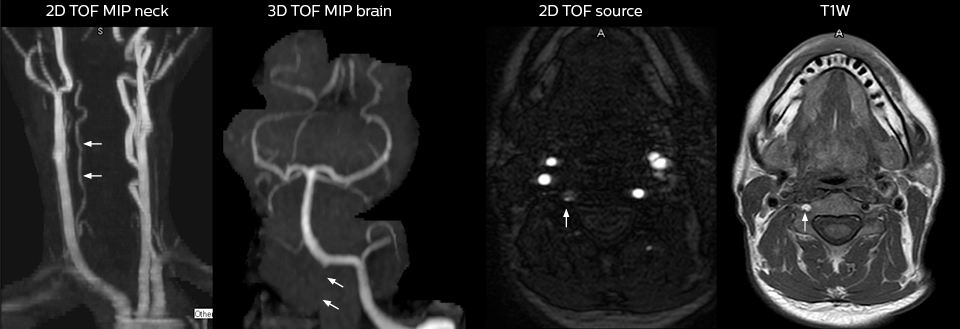

2. Grimm JM, Schindler A, Schwarz F, Cyran CC, Bayer-Karpinska A, Freilinger T, Yuan C, Linn J, Trelles M, Reiser MF, Nikolaou K, Saam T. Computed tomography angiography vs 3 T black-blood cardiovascular magnetic resonance for identification of symptomatic carotid plaques. J Cardiovasc Magn Reson. 2014;16:84.